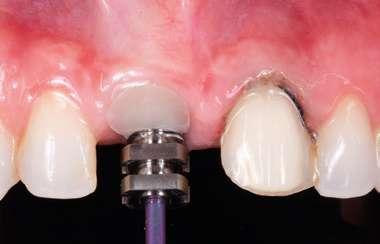

Con toda nuestra cirugía perfectamente diagnosticada y planificada solo nos queda ejecutarla. 1.- Quitamos la corona ferulizada.

2.- Extraemos de manera meticulosa la raíz del diente afectado.

3.- Legramos toda la zona del lecho implantario con el fin de poder eliminar cualquier resto de tejido de granulación.

4.- Desepitelizamos en margen gingival.

5.- Tunelizamos el defecto vestibular para alojar el injerto de tejido conectivo.

6.- Colocamos injerto de tejido conectivo.

7.- Interponemos membrana reabsorbible entre tejido conectivo y alveolo.

8.- Realizamos osteotomía mediante férula quirúrgica utilizando fresa piloto.

21 eldentistamoderno mayo/junio 2024

caso clínico

9.- Seguimos preparando el lecho utilizando fresado biológico con la OsseoShaperTM

10.- Colocamos implante Nobel Biocare N1TM TiUltra de 3,5x13.

11.- Observamos el torque obtenido de 50N por lo tanto podemos realizar carga inmediata.

12.- Colocamos aditamento N1TM Base XealTM con el fin de trabajar la prótesis a nivel gingivall.

13.- Colocamos pilar provisional.

14.- Rellenamos el gap con creos xenogainTM, compactando para que el hueso llegue lo más apical posible y cubra la superficie implantaria expuesta.

15.- Cortamos pilar provisional y adaptamos el TempShellTM con composite. Podemos comprobar la predictibilidad en cuanto a la posición 3D planificada de nuestro implante.

DIGITAL EN IMPLANTOLOGÍA 22 eldentistamoderno mayo/junio 2024

WORKFLOW

16.- Colocamos restauración provisional atornillada y fuera de oclusión y traccionamos hacia coronal de los tejidos.

17.- Verificamos nuestro tratamiento con CBCT.